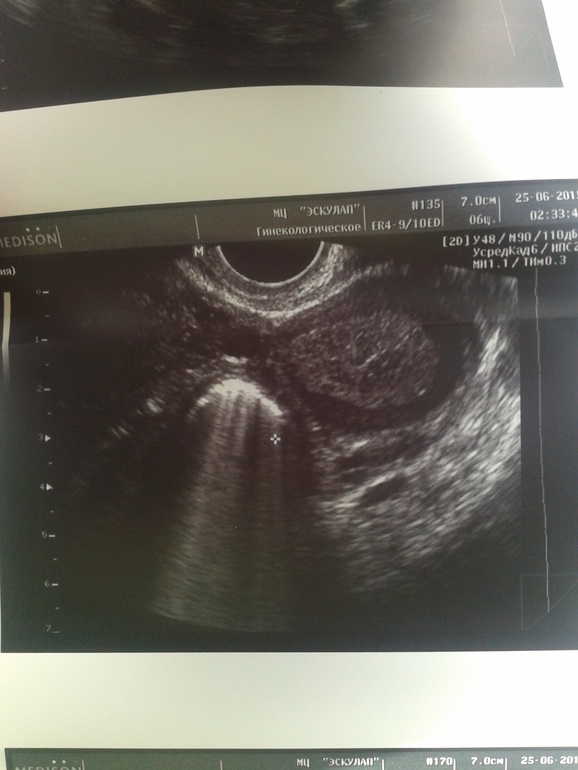

Гинекология (кроме тем беременности)Сегодня 11-й день цикла. Ходила на узи. И вот какой результат. На правом яичнике доктор обнаружила ретенционную кисту 18х15мм. Сказала, что надо на 5-й день цикла сделать узи, чтобы уже точно подтвердить диагноз. А так вроде как похоже и на кисту и на жёлтое тело. Девочки, что скажите, может было у кого такое? И ещё вопрос, может покажется кому глупым: жёлтое тело когда образуется? Что то я ничего в этом не понимаю

Желтое тело образуется после овуляции на месте лопнувшего фолликула, бывает так что он образуется в кисту, у меня щас что то подобное происходит похоже. Пока не кипишуйте, ждите месячных на 5 день переделайте, может уйдет, всяко бывает. Раньше вам точно ничего никто не скажет. Может овуляция раньше пришла и желтое тело образовалась фиг его знает, я щас тоже хожу по врачами со своими кистами что за напасть такая жуть...